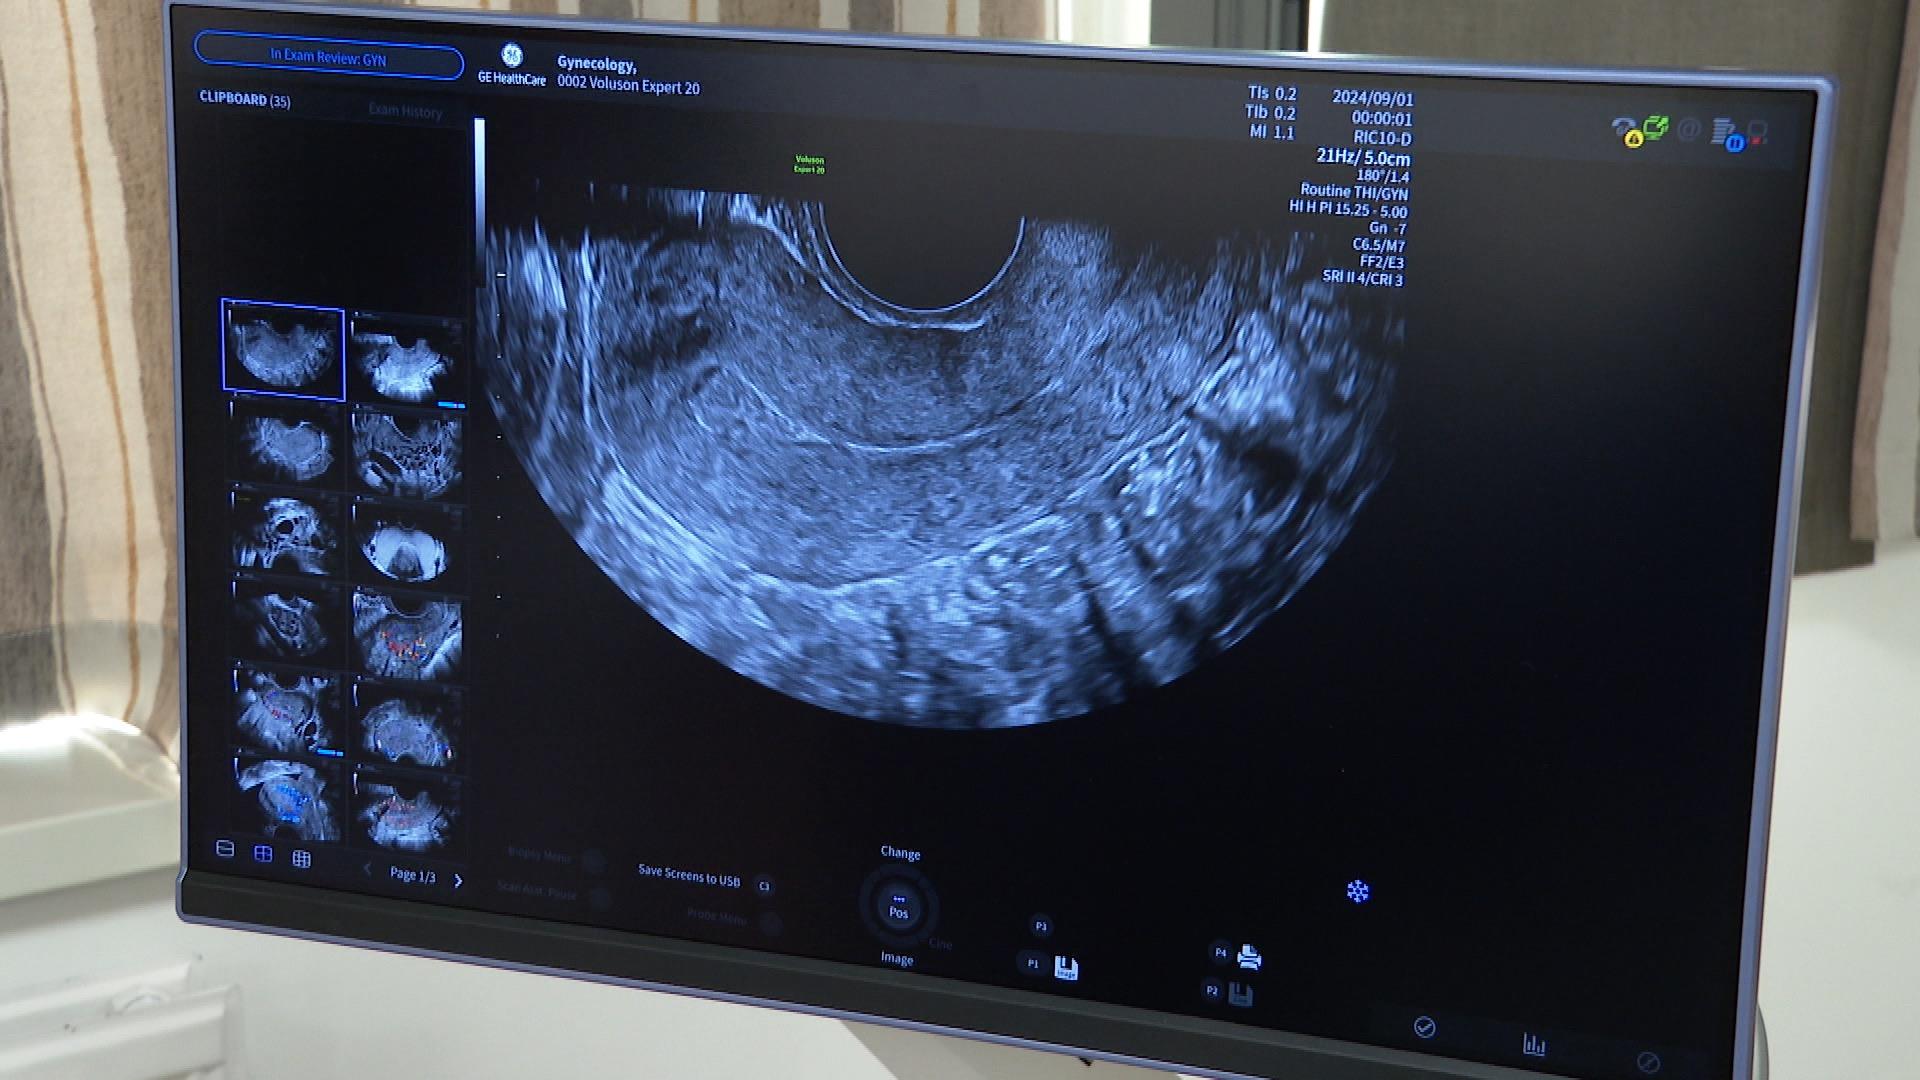

Ma már az új genetikai ultrahanggal vizsgálták a kismamákat. A mesterséges intelligenciával támogatott eszköz a korábbinál jóval részletesebb képet ad, számos automatikus beállítása segíti a pontos diagnosztikát. A 75 millió forintos készüléket ünnepélyes keretek között adták át.

Két okból is hatalmas előrelépést jelent. Egyrészt azért, mert ez egy csúcsminőségű ultrahang, közel bruttó 75 millió forint értékben. Több fejjel és így 3D-s, 4D-s ultrahang vizsgálatra is alkalmas. Tehát alkalmas arra, hogy meddő párokat kivizsgáljunk, hölgyeket és férfiakat is, és arra is alkalmas, hogy magzati, genetikai szűrővizsgálatok történjenek